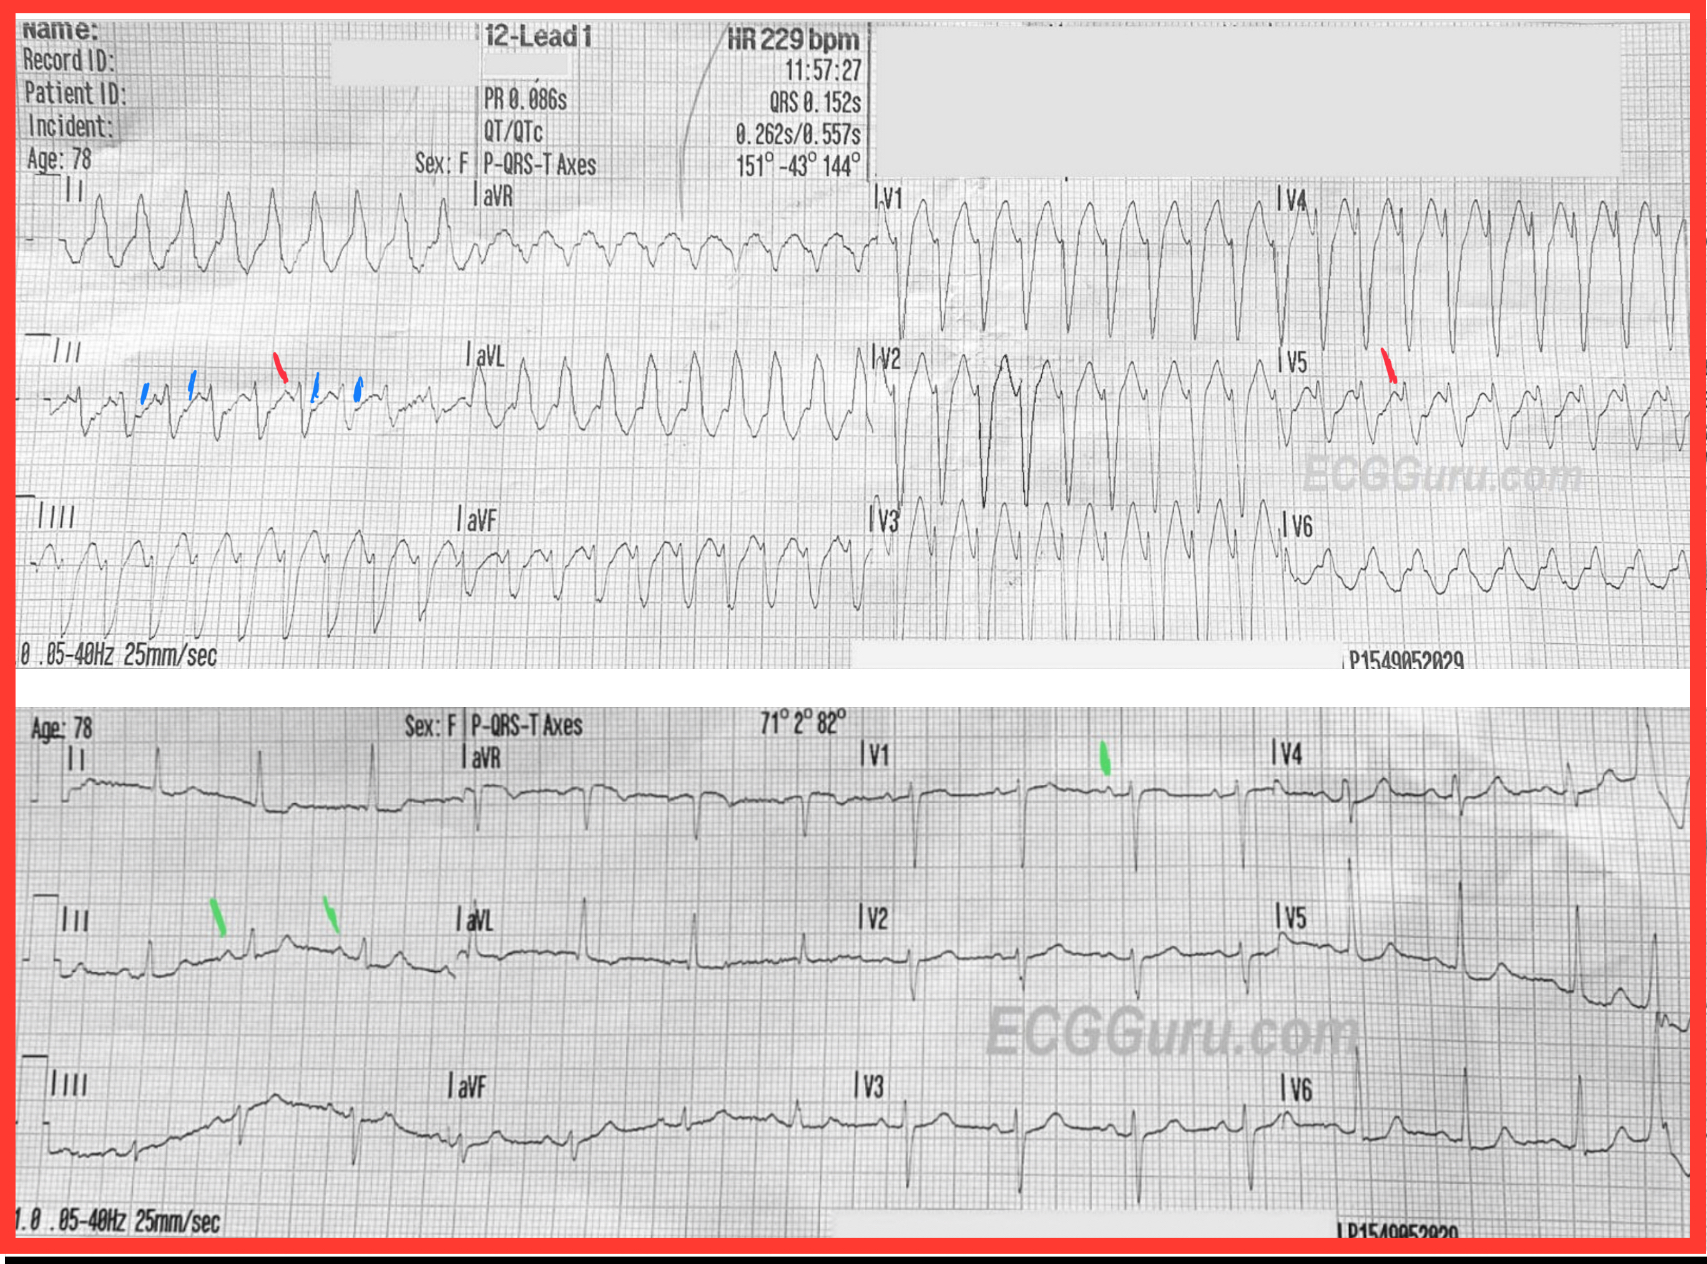

ECG Number 1, 11:57 a.m.: There is a wide-complex tachycardia at a rate of about 230 bpm. The QRS is .15 seconds (150 ms). The QRS frontal plane axis is leftward. P waves are not readily seen, but the computer gives a P axis and PRI. The PRI given is taken from Lead II, which, along with V5, does have P waves. In the other leads, the P waves are buried in preceding T waves. This photo shows an ECG that is not lying flat, so it is difficult to line up the complexes. Normally, it helps to look at the leads above or below to determine where waves begin and end, as all three channels are run simultaneously. The QRS complexes have a “typical” left bundle branch block morphology, with an rS complex in V1 and a monophasic R wave in Leads I and V6. The T waves are “discordant”, they are in the opposite direction from the QRS complexes, which is typical of LBBB.

For clarity — I’ve put ECG #1 together with ECG #3, with a few added labels. I interpreted ECG #1 as showing a regular WCT at ~225/minute, without clear sign of P waves. To EMPHASIZE — identifying sinus P waves in a rhythm this fast is difficult, because of how short R-R intervals are. But I thought the PR interval would be too short if the upright deflection I’ve labeled with a RED line were to be a sinus P wave. In my experience — you’ll virtually never see P waves in lead V5 but not in leads V1, III, aVF — so I do not think there are sinus P waves, but instead just prominent T waves that simulate P waves because the rate is so fast. (NOTE: Against the RED lines being P waves is the reality that sinus tachycardia will not attain a rate of 225/minute in a 78 year woman …).

Instead — I suspected in my initial review of ECG #1 that the BLUE lines in ECG #1 represented retrograde P waves. I fully acknowledge it is impossible to prove this — but I believe the course of events in today’s case IS consistent with my assumption of retrograde P waves with a short RP’ interval in this patient with AVNRT.

I completely agree with Dawn that QRS morphology in ECG #1 is perfectly consistent with LBBB conduction. Not only are monophasic all upright R waves present in lateral leads I,aVL,V6 — and a predominantly negative QRS complex in right-sided lead V1 — but predominant negativity of the QRS extends to lead V5 — and the SLOPE of the downslope of the S waves in V1-thru-V4 is very steep, all consistent with supraventricular LBBB conduction.

BOTTOM LINE: Nothing is 100% — but given such typical QRS morphology for LBBB conduction AND what I perceive as 1:1 retrograde (V:A) conduction — I thought the rhythm diagnosis of ECG #1 most likely to be AVNRT with QRS widening manifesting LBBB conduction due EITHER to preexisting LBBB — OR — to LBBB aberration.

The patient was electrically cardioverted — and sinus rhythm was restored. Note that the PR interval is clearly longer in the post-conversion tracing than in ECG #1 (GREEN lines). Note also that with sinus rhythm — definite sinus P waves are also seen in leads III,aVF and V1. While true that the PR interval does shorten with tachycardia — it does not usually shorten as much as it would have to if the RED arrows in lead II of ECG #1 were P waves.

As per Dawn — a PVC is seen at the end of the post-conversion tracing — with a different QRS morphology than for the WCT (ie, the QRS is all positive in leads V4,5,6 for this PVC — whereas there should be predominant negativity in leads V4,V5 if there was LBBB conduction).

NOTE: The fact that with sinus rhythm in the post-conversion tracing the QRS is narrow — tells us that the reason for LBBB conduction during the tachycardia was not “preexisting BBB” — but rather rate-related LBBB aberration.